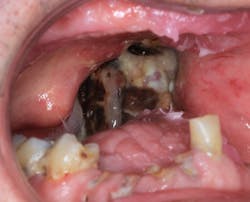

After recovering from that introduction, it turns out that this 71-year-old gentleman was diagnosed with and has been treated for tonsillar cancer that had spread almost to his entire head-and-neck area. The cancer was supposedly gone in 2012 with radiation and chemotherapy, but as karma would have it, it returned with a vengeance (see photo), and the prognosis is not good. Despite this, his chief complaint was just that he wanted to chew his food better. That’s it. So in order to help him achieve this goal, I’m going to go against all the rules of dentistry to get him to a state that at least improves his status quo.

You see, this patient has a full upper denture, broken carious teeth on the lower, and he is not a candidate for extractions due to the high risk for osteoradionecrosis. He also opens only two inches, which makes restorative work nearly impossible. What would you do?